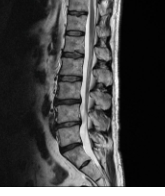

3. 디스크의 손상: 디스크는 척추의 각 뼈 사이에 위치하고 있으며, 뼈를 서로 붙이고 충격을 흡수합니다. 디스크가 손상을 받거나 균열이 발생하면 인접한 신경과 충돌하여 통증을 유발할 수 있습니다.

5. 추간판의 변형: 추간판은 척추의 뼈 사이에 위치하고 있으며, 뼈를 서로 붙이고 충격을 흡수합니다. 추간판이 변형되거나 압박을 받으면 통증이 발생할 수 있습니다.

허리디스크는 척추 디스크가 손상되어 디스크 내부의 젤 상태의 물질이 디스크 외부로 누출될 때 발생하는 질환입니다. 이러한 디스크 누출은 신경 자극을 유발하며, 이에 따라 다양한 증상이 나타날 수 있습니다.